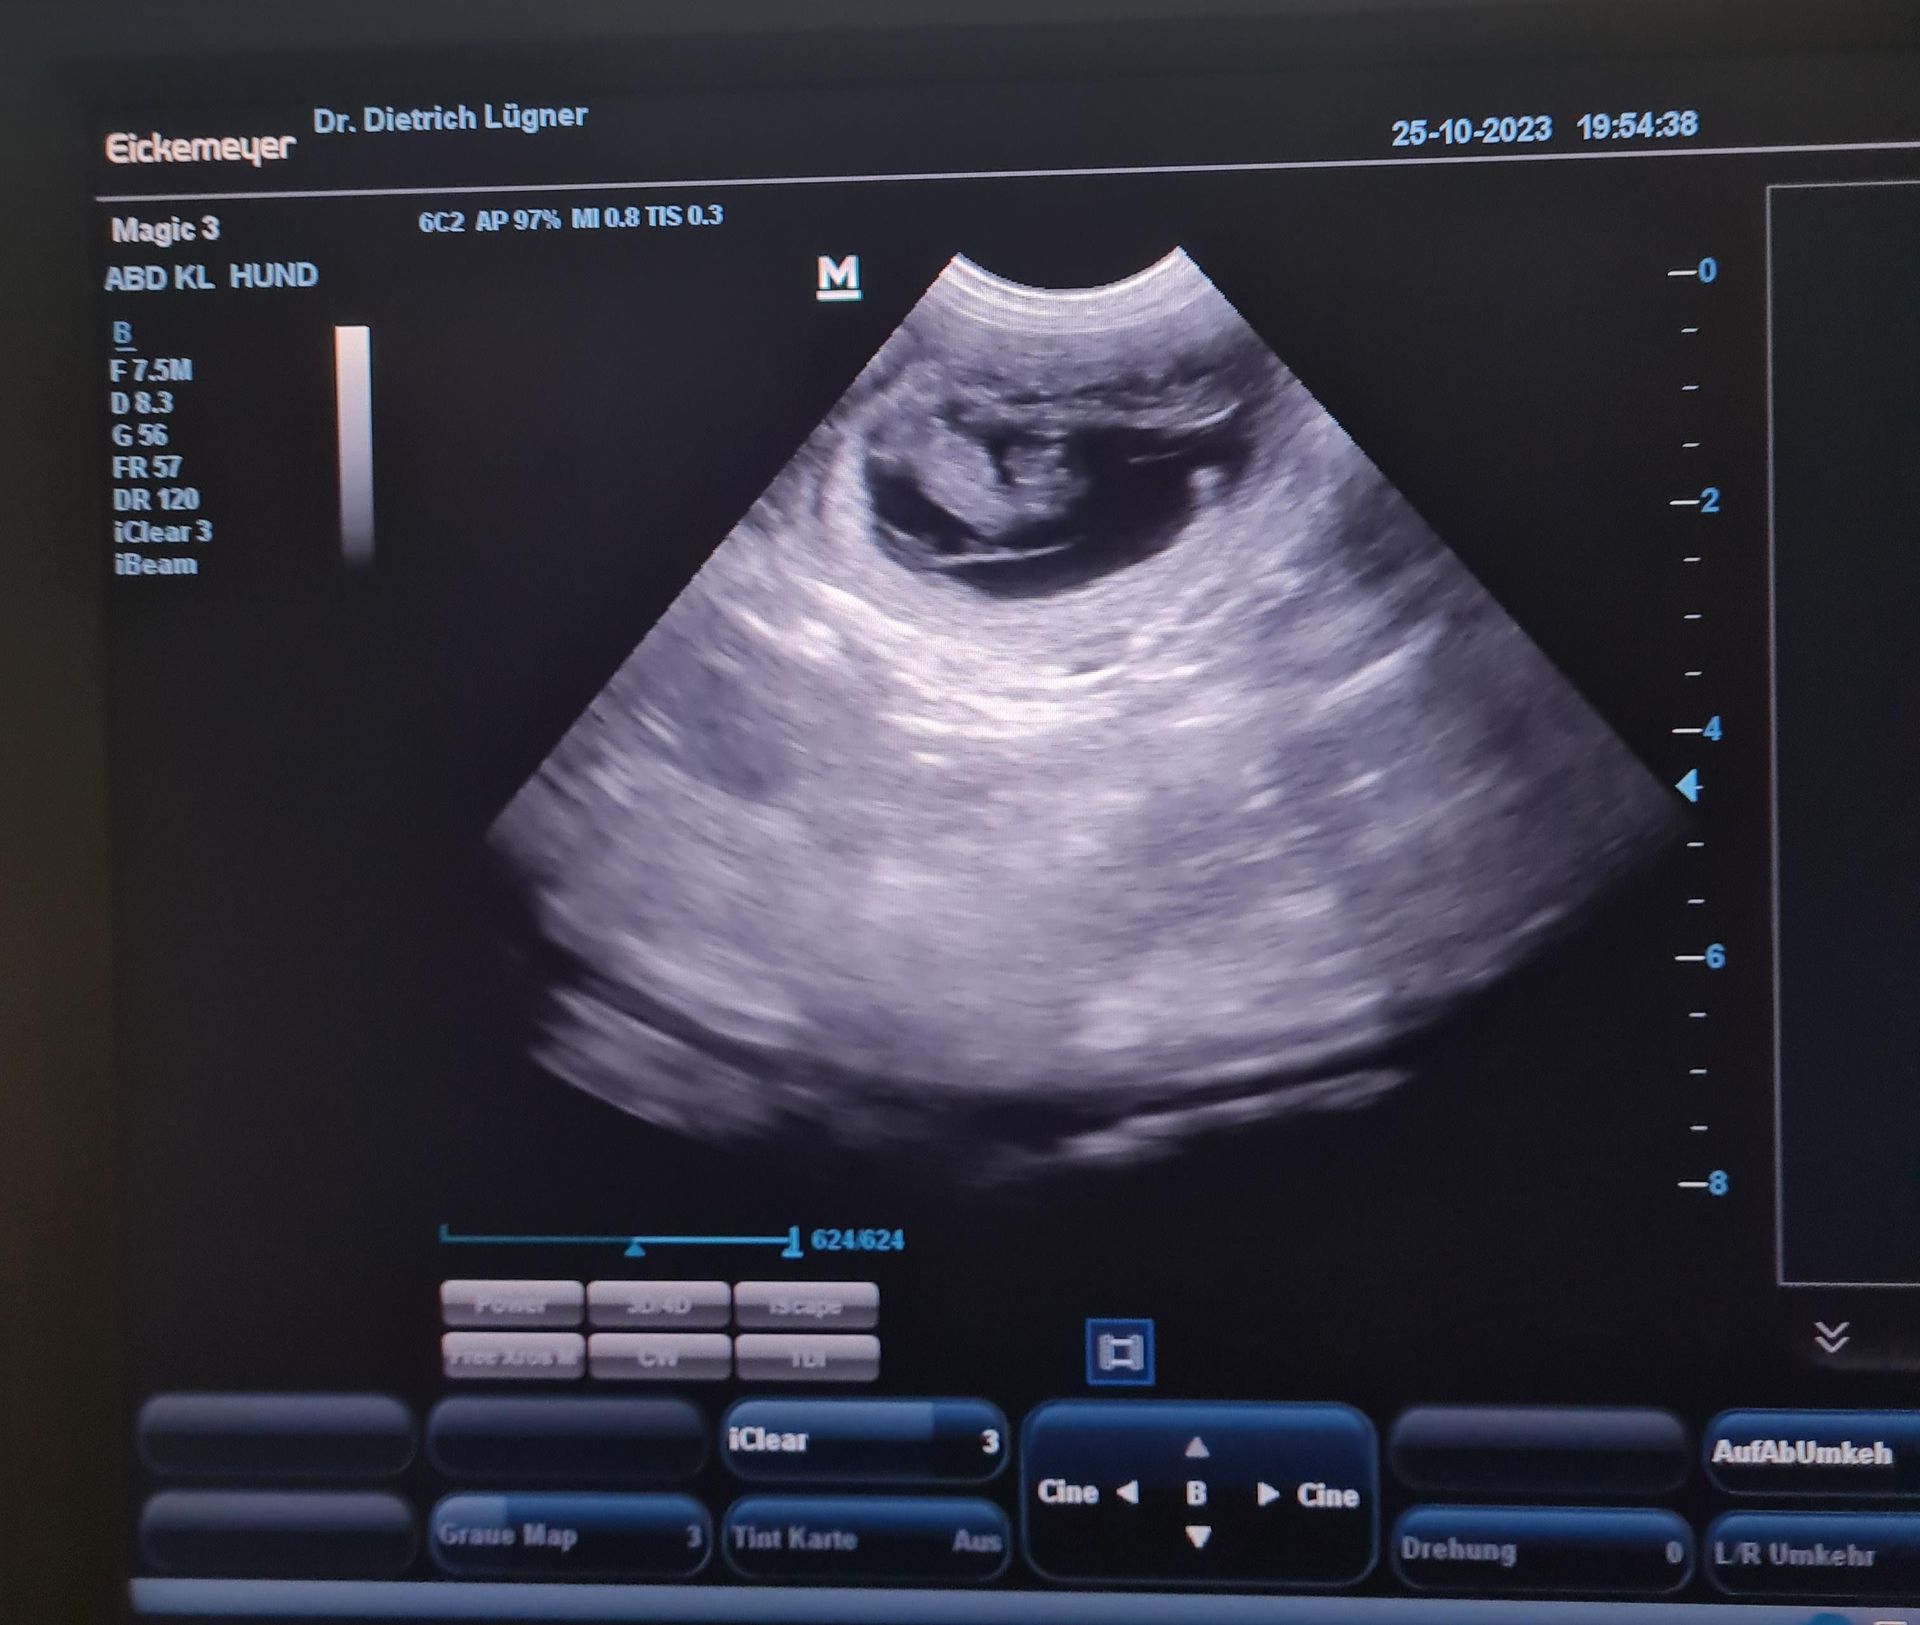

25.10.2023

Ultra ist tragend! Somit erwarten wir unseren A-Wurf Ende November.